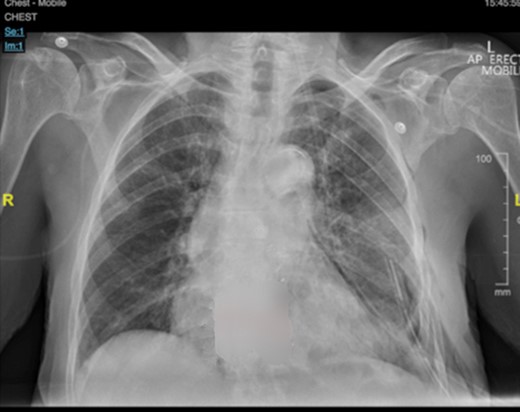

The patient was extubated postoperatively and transferred to the ward. She recovered well, and began mobilizing on postoperative day 1. The chest drain was removed on postoperative day 2 after complete lung re-expansion (Fig 5). Paravertebral catheter was removed on postoperative day three, and the patient transitioned to oral analgesia without issue. There were no postoperative complications, and the patient was discharged home on postoperative day 4.